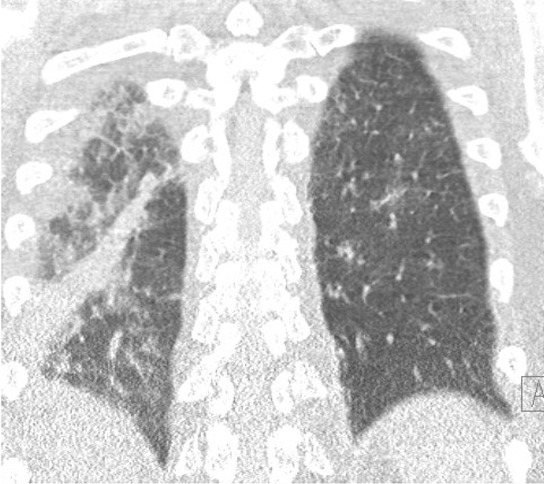

The patient was transferred to the intensive care unit (ICU) and amoxicillin-clavulanic acid was initiated. Blood testing highlighted an inflammatory syndrome [C-reactive protein (CRP) between 70 and 90 mg/L, < 10] and hepatic cytolysis and cholestasis evoking liver involvement. Sediment and urinary cultures were negative. Blood cultures for mycobacteria were done after nightly fever peaks. Empirical anti-tuberculous treatment was started associating isoniazid, rifampicin and vitamin B6 in the event of a BCGitis. Chest X-Ray (Figure 1) showed an interstitial syndrome.

Chest X-ray

At that time, the lung symptoms came with cough and grade II dyspnea with a bilateral pneumonia associated with pleural effusion on the lung tomodensitometry. A bronchoscopy together with a bronchoalveolar lavage (BAL) with Ziel and auramine colorations as well as trans-bronchial biopsies were performed. Four days later, the mycobacterial research came back negative and cytology highlighted inflammatory trails with the presence of granulocytes.

Thoracic tomodensitometry

In the first place, the non-specific signs such as inflammatory syndrome,[5] increased liver enzymes and lung damage (pulmonary auscultation may reveal a crackling, chest x-ray can show an interstitial syndrome and atelectasis, chest tomography scan determining the precise topography of the lesions) can be observed.

Second, it is possible to spot specific evidences of systemic BCGitis such as cultures of Mycobacteria and PCR in the urines (blood and BAL could all be negative, Ziel and Auramine colorations are generally negative,[5] intradermal reaction is generally negative.[3] If a lung damage is present: histopathology and cytology analysis may reveal the presence of bronchial granulomas (only in 40% of biopsies). Alcohol-resistant bacilli can be rarely highlighted by coloring (Ziehl or others). The diagnosis is generally acquired through pathology and obtained via bronchial, hepatic or prostatic biopsies showing the presence of granulomas.[5] In many cases, these tests are also negative and it is recommended to start antituberculosis antimicrobials empirically in case of clinical suspicion of the disease.[6] In our case, the patient presented an inflammatory syndrome associated with increased liver enzymes. At the onset of the symptoms, lung auscultation revealed a crinkly. Radiography has highlighted the presence of a basal infiltrate right and the thoracic tomographic scanner made it clear that the lesions were bilateral. The specific enzymatic coloration came back negative. Bronchial biopsies were collected but were not contributive to the diagnosis as showing no evidences of granulomas. Polymerase chain reaction (PCR) has not been carried out on samples.